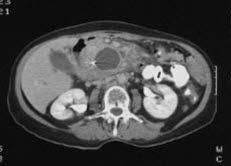

CT-bilde av bukspyttkjertel med svulstUltralyd ble før mye brukt til å granske bukspyttkjertelen, men fordi tarmluft ofte forstyrrer ultralydundersøkelsen blir nå CT eller MR som regel foretrukket. Bukspyttkjertelen forløper hos de fleste litt skrått oppover mot venstre med "hodet" mot tolvfingertarmen og med "halen" mot milten. Den normale utførselsgangen som går fra bukspyttkjertelen til tolvfingertarmen, er ofte så vidt synlig på CT. Det er noe variasjon i form og størrelse på bukspyttkjertelen fra person til person.

Kreft i bukspyttkjertelen befinner seg i to av tre tilfeller i "hodet" på kjertelen - den delen som ligger an mot tolvfingertarmen. Røntgenlegen kan se fortetninger som endrer omrisset av kjertelen. Bildene blir tydeligere etter innsprøyting av kontrast i blodet. Undersøkelsen kan også vise om det er innvekst i naboorganer, eventuelt om det er spredning til leveren.